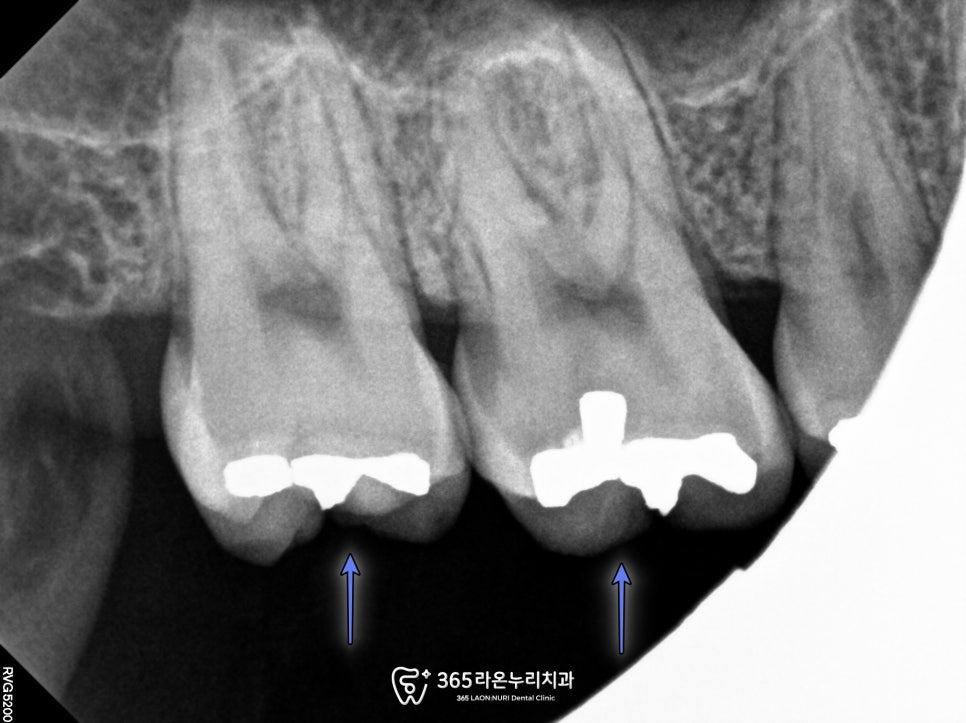

신장동 치과 에서는

방사선 불투과성 재료인

아말감 밑으로 충치가

진행된 것을 확인됩니다.

신장동 치과 에서

더 자세하게 검진을 해봤을 때

다행히 치수 손상 가능성은 안보였습니다.

2025. 03. 20

다행히도 아말감을 제거 후

확인해 봤을 때도

충치 범위가 크지 않아

많은 삭제 없이

레진 및 인레이를 통해

수복을 진행하였습니다.